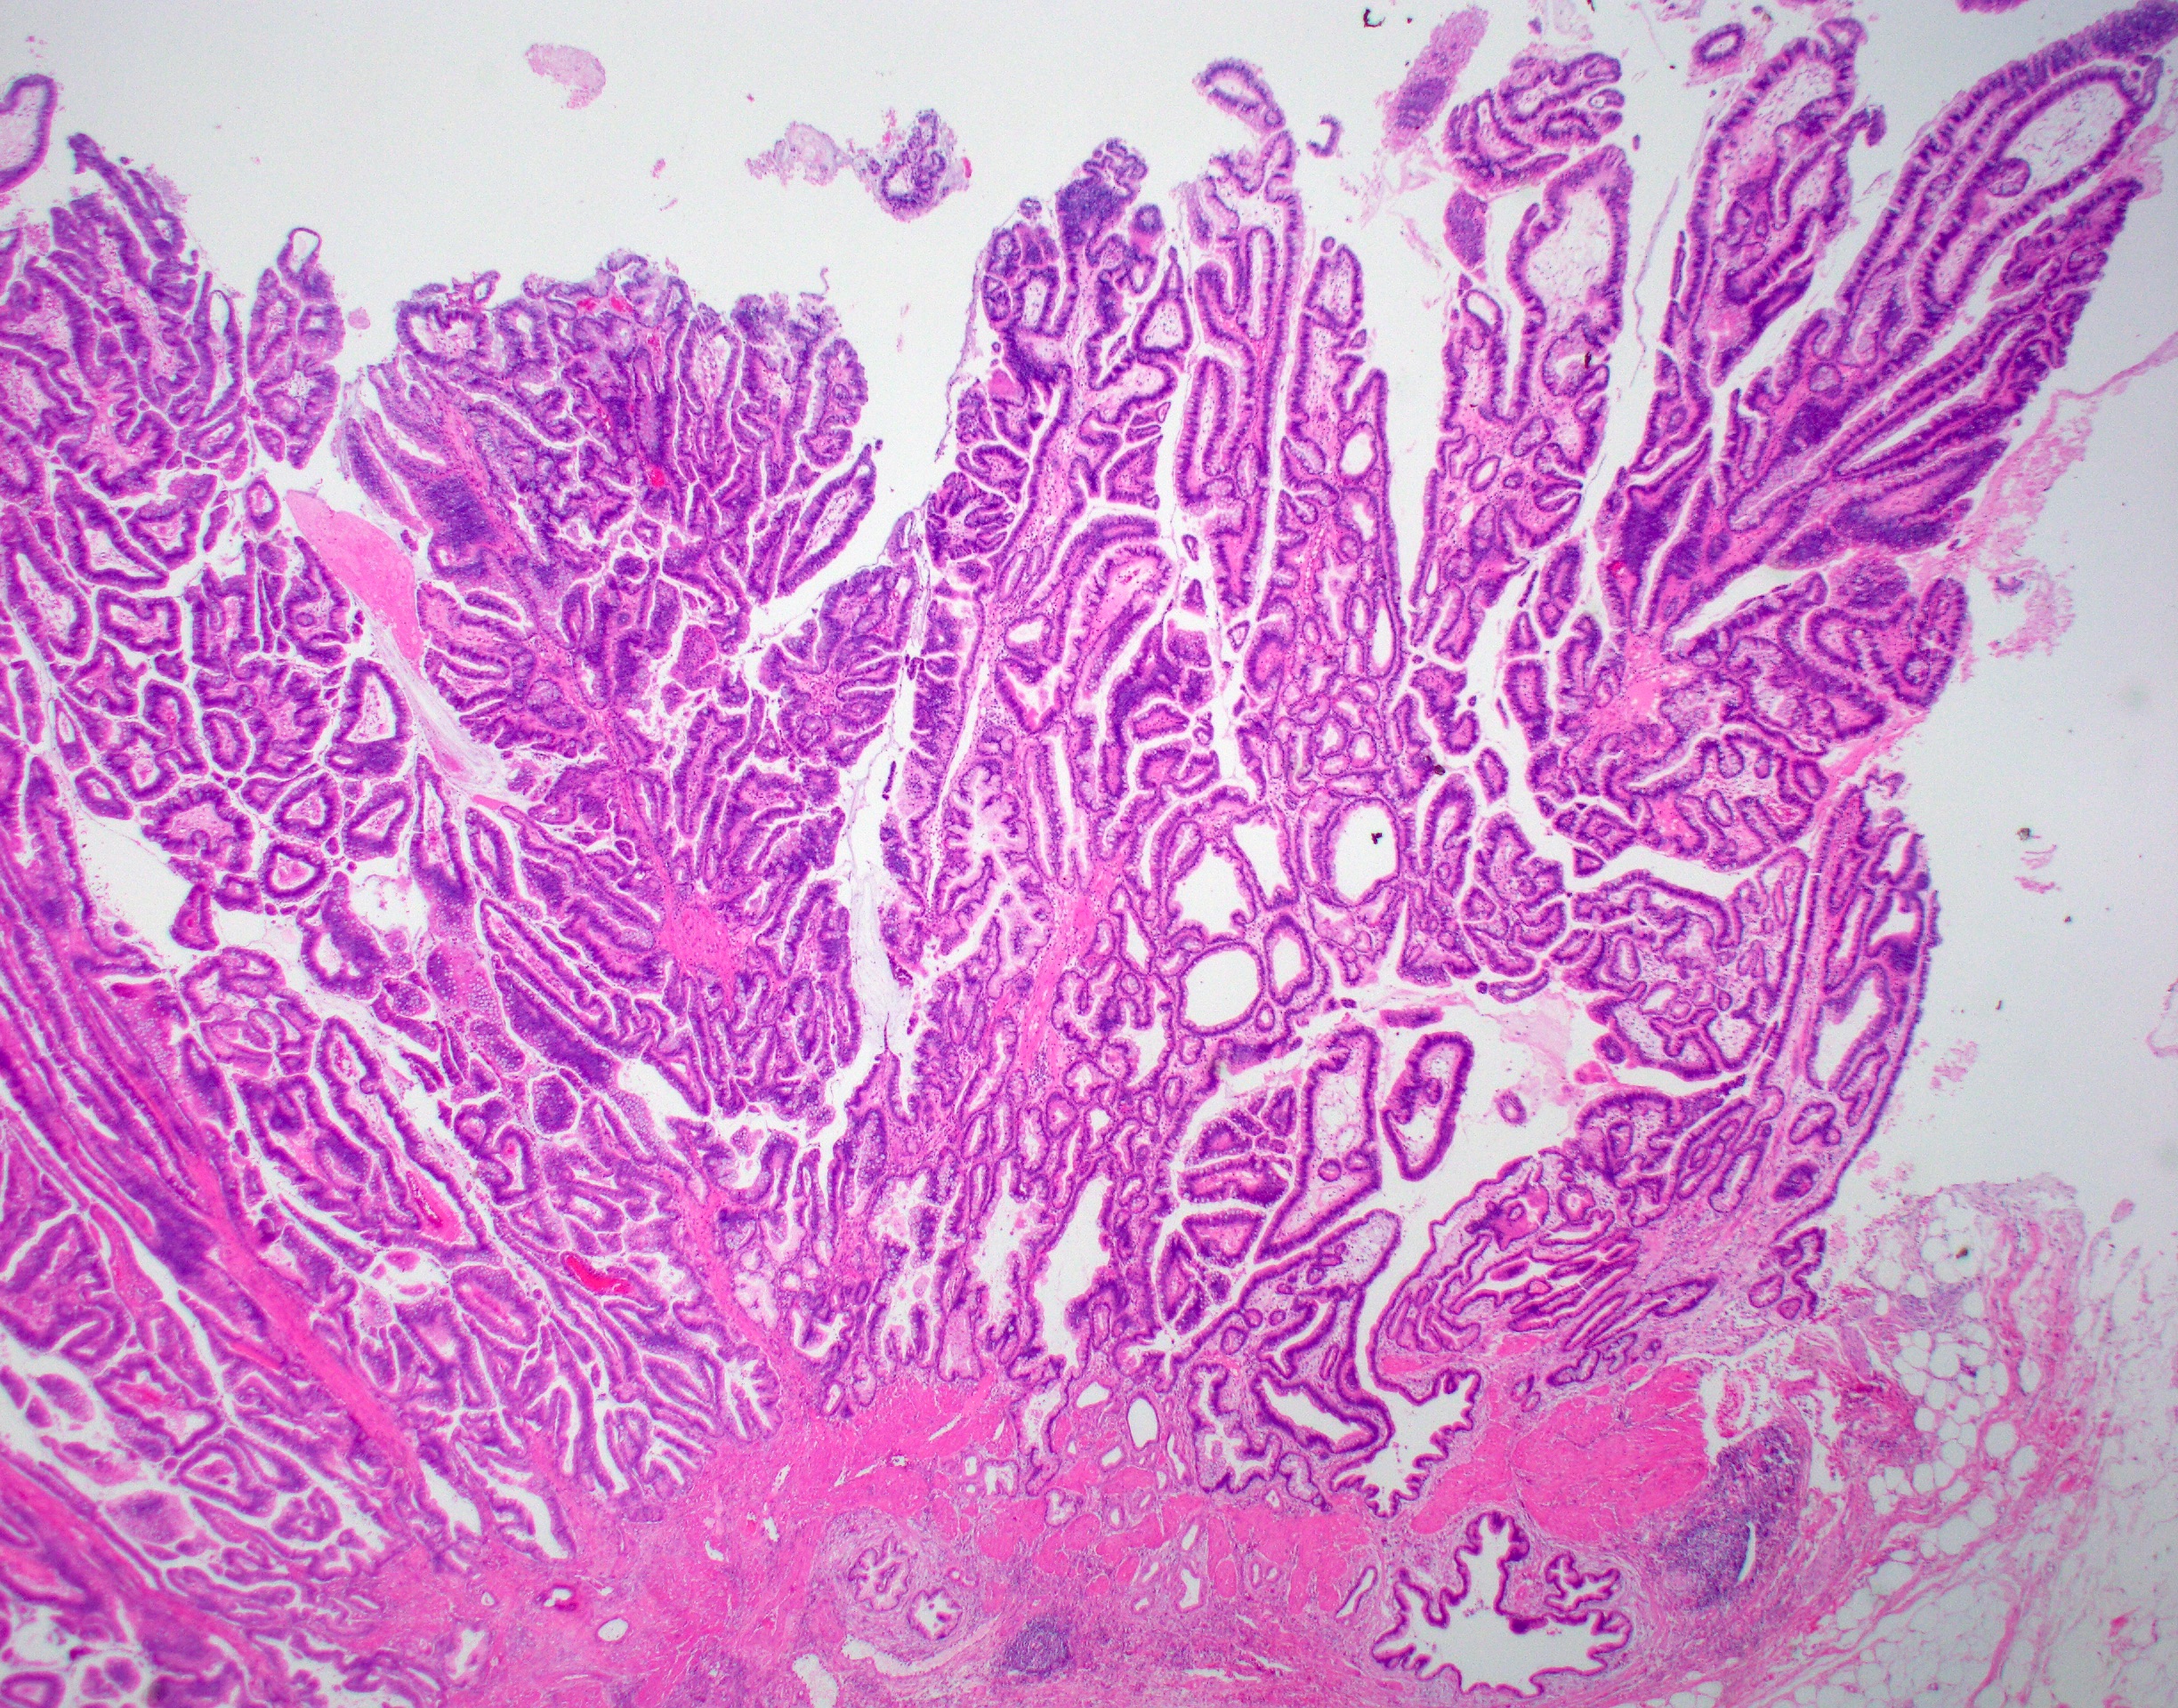

Фотографии опухоли медуллярной аденокарциномы

Раздел: Снимки-откровения